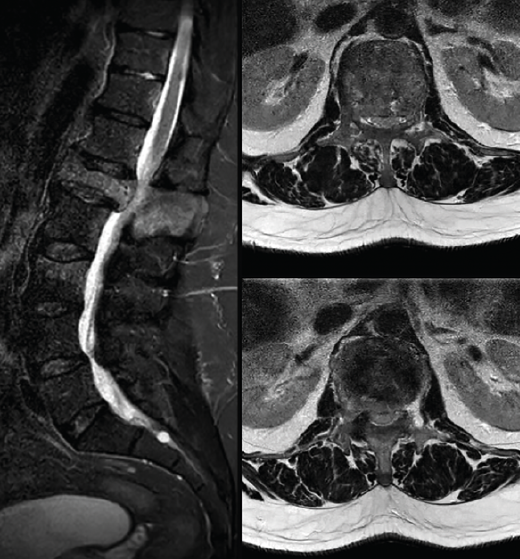

Tras los hallazgos en la TAC, surgen dudas sobre el diagnóstico y se completa el estudio con una resonancia magnética (RM) (Figura 3) en la que se corrobora la presencia de una fractura vertebral sobre un cuerpo vertebral peculiar. Sin embargo, en la secuencia STIR no se aprecia el edema que se esperaría en una fractura aguda. También se observa una marcada hipertrofia de los elementos vertebrales posteriores, cierta captación al nivel de las apófisis articulares, así como el aspecto heterogéneo del cuerpo vertebral. Todos estos hallazgos radiológicos apuntan a la posibilidad de estar ante una fractura crónica sobre una vértebra patológica, concretamente se sospecha que pueda ser una enfermedad de Paget vertebral (EP).

Figura 3. Resonancia magnética de columna lumbosacra, secuencia STIR. Corte sagital: hiperintensidad tenue y difusa en L1 con ocupación del canal > 50%. Cortes axiales: focos de lisis y esclerosis en diferentes niveles del cuerpo de L1, hiperintensidad en el pedículo izquierdo, típico de fractura crónica.